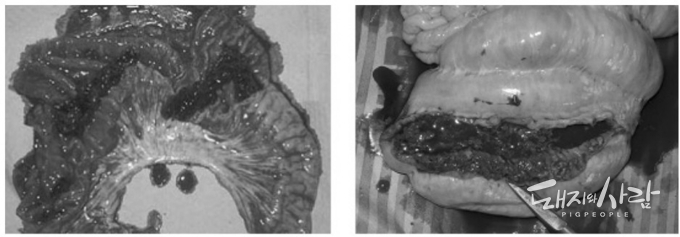

'돼지 증식성 장염(PPE)'은 Lawsonia intracellularis에 의해 유발되는 전염성 위장관 질환이다. 임상적으로 PPE는 성장기 돼지에서 출혈성 설사를 유발하며 때로는 폐사에 이르게 한다. 하지만, 질병이 만성 단계로 진행되면 감염된 돼지는 더 이상 뚜렷한 증상을 보이지 않는다.

검사 건수별로는 420개의 분변 검체 중 113개(26.9%)가 PPE 양성으로 확인되었다. 1,075개의 점막 스크래핑 검체 중 109개(10.1%)가 PPE 양성으로 확인되었다. 총 1,495개 검체 중 222개(14.8%)가 PPE 양성으로 확인되었다.